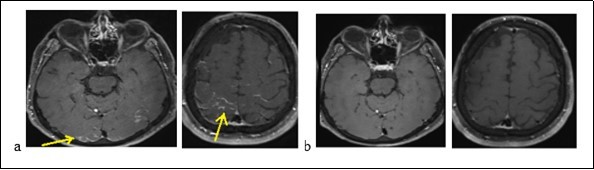

Mr. P.B., a man of 56, suffering from a left sudden hemiparesis within 30 minutes, was admitted to hospital on September 21, 2017. The beginning was marked by a feeling of head emptiness and unusual serious headache during a flight. This headache was followed by gradual paraesthesia of the left hemibody, moving from the vertex to the lower limbs. A left hemiparesis and speech disturbance resulted from paraesthesias. These symptoms decreased about 10 minutes. The plane had landed under an emergency condition and the patient was admitted to stroke emergency unity. There is a need to say that he had no history of vascular pathology before. On test, the result showed that blood pressure was 144/96 mm Hg. Consciousness of the patient was normal with good temporo-spatial orientation. Besides, Neurological test and other tools were normal. The routine biological test was normal too: the blood count, the C-reative Protein (CRP), blood urea, creatinine, ionogram, transaminases and gammaglutamyl transferases were normal. There was no abnomalies in the immunological assessment (antinuclear, anti cardiolipids, anti B2 GP1, circulating anti-body of lupus type, ANCA and native anti DNA). The serologies: Human immunodeficiency virus (HIV), Syphilis, Lyme, viral hepatitis C and B (HVC, HVB ) were negative. The cerebro-spinal fluid (CSF) was normal. A brain MRI (Figure 1a) displayed a cortical contrast enhancement in relation with possibly pial leptomeningeal involvement, some hypersignals on Flair sequences of frontal and parietal subcortical white matter. An assessment of pachymeningitis with a thoraco-abdomino-pelvic scanner and an electroencephalogram (EEG) were normal. The cerebral MRI (Figure 1b) after 8 days had shown a complete regression of the lesions. We noted that the diagnosis of an RPE syndrome facing the serious onset of symptoms, the MRI findings and the complete decrease of the lesions.

Figure 1.Brain MRI displaying occipital cortical hypersignals in Flair sequences (a) and decrease of lesions (b)

Brain MRI displaying occipital cortical hypersignals in Flair sequences (a) and decrease of lesions (b)